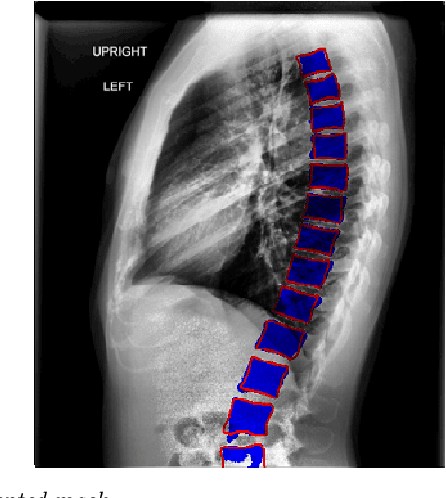

Abstract:The purpose of this study is to develop an automated algorithm for thoracic vertebral segmentation on chest radiography using deep learning. 124 de-identified lateral chest radiographs on unique patients were obtained. Segmentations of visible vertebrae were manually performed by a medical student and verified by a board-certified radiologist. 74 images were used for training, 10 for validation, and 40 were held out for testing. A U-Net deep convolutional neural network was employed for segmentation, using the sum of dice coefficient and binary cross-entropy as the loss function. On the test set, the algorithm demonstrated an average dice coefficient value of 90.5 and an average intersection-over-union (IoU) of 81.75. Deep learning demonstrates promise in the segmentation of vertebrae on lateral chest radiography.